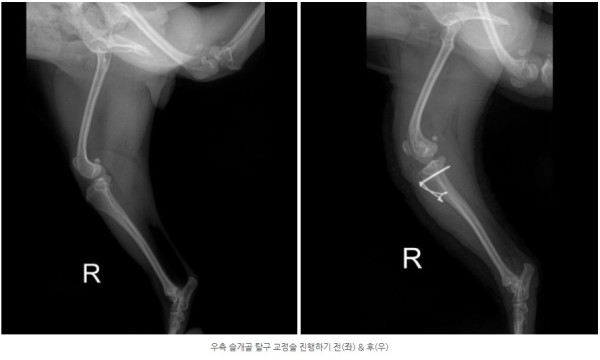

정확한 상태 확인을 위한 검사를 진행한 결과,

양쪽 모두 안쪽으로 슬개골이 빠지는 내측탈구 4기 상태가 확인되었고

통증의 근본 원인을 해결하기 위해 양측 모두 슬개골 탈구 교정술(MPL)을 진행하기로 결정하였습니다.